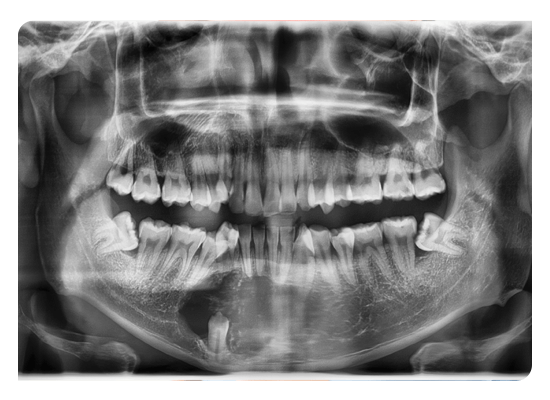

Gömülü 20 Yaş Dişleri

20 yaş dişleri genellikle 17-25 yaşları arasında sürerler. Sürme yaşı tamamlandığı halde diş kavsinde yerini alamamışlar ise gömülü 20 yaş dişleri olarak adlandırılırlar. Günümüz insanının çene yapısı önceki çağlarda yaşayan insanlara göre daha küçük olduğundan ve beslenme alışkanlıkları değişkenlik gösterdiğinden 20 yaş dişlerinin gömülü kalmasına daha sık rastlanılmaktadır.

Dişeti hastalıklarının meydana gelmesi: Gömülü yirmi yaş dişi, komşulukta olduğu dişin kemik desteğini zayıflatır ve o bölgede besin artığı birikimine sebep olabilir.

Diş çürüklerinin meydana gelmesi: Yarı sürmüş 20 yaş dişleri, komşuluğunda yer alan diş ile aralarında gıda birikimine ve buna bağlı olarak diş çürüklerine neden olabilir.

Kist ve tümörlerin meydana gelmesi: Gömülü diş tamamıyle kemiğin içerisinde kaldığında dişe ait kese de onunla birlikte kalmaktadır. Folikül adı verilen bu keseden kistik bir oluşum ya da tümör gelişebilir.